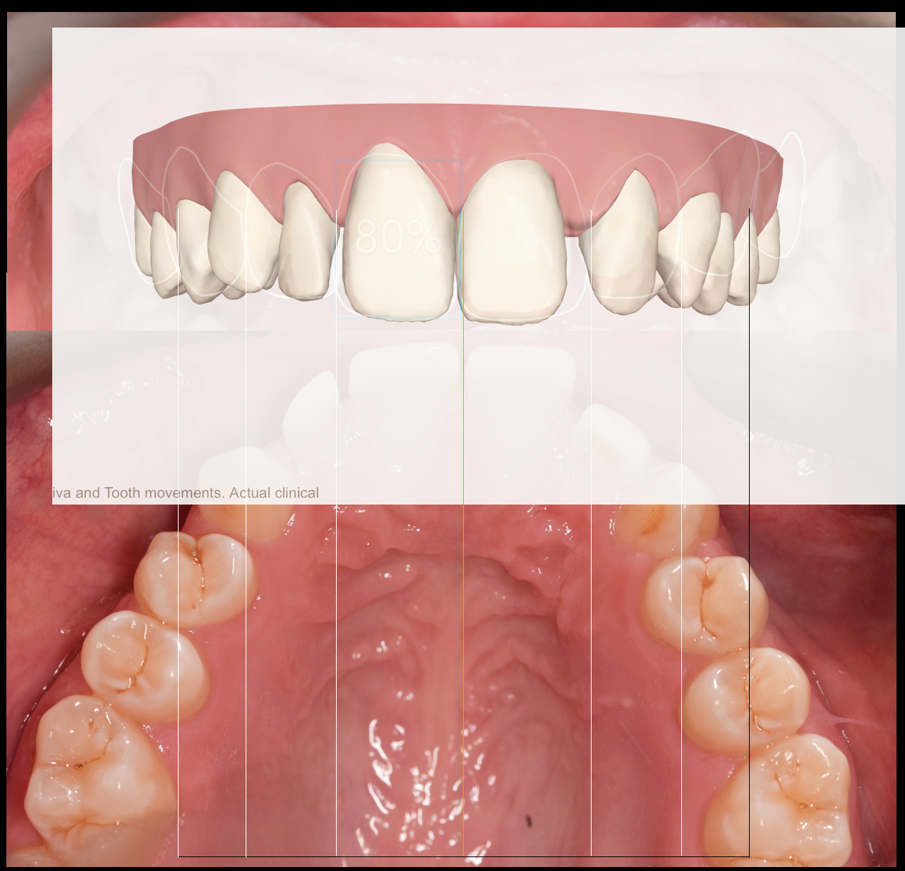

A treatment plan was constructed based on a facially driven smile design, with calibrated images measured against the invisalign clincheck software. The benefit to using a digital system here was to allow for accurate positioning of the anterior teeth for minimal preparation and the ideal restorative outcome. (Figs. 1a-f)

A 7 week invisalign programme allowed for enough movement in the upper arch, while resolving the mild crowing in the lower arch. The final tooth position can be seen in figure 1f.

Post-ortho provisional retention was implemented with removal essix retainers which were used for home whitening of the upper and lower teeth. A final shade of BL3 was achieved, after 10 days of rehydration. In this time the lab created a diagnostic wax up guided by the smile design. A putty matrix was used to transfer the wax up to a trial smile (Fig. 2).